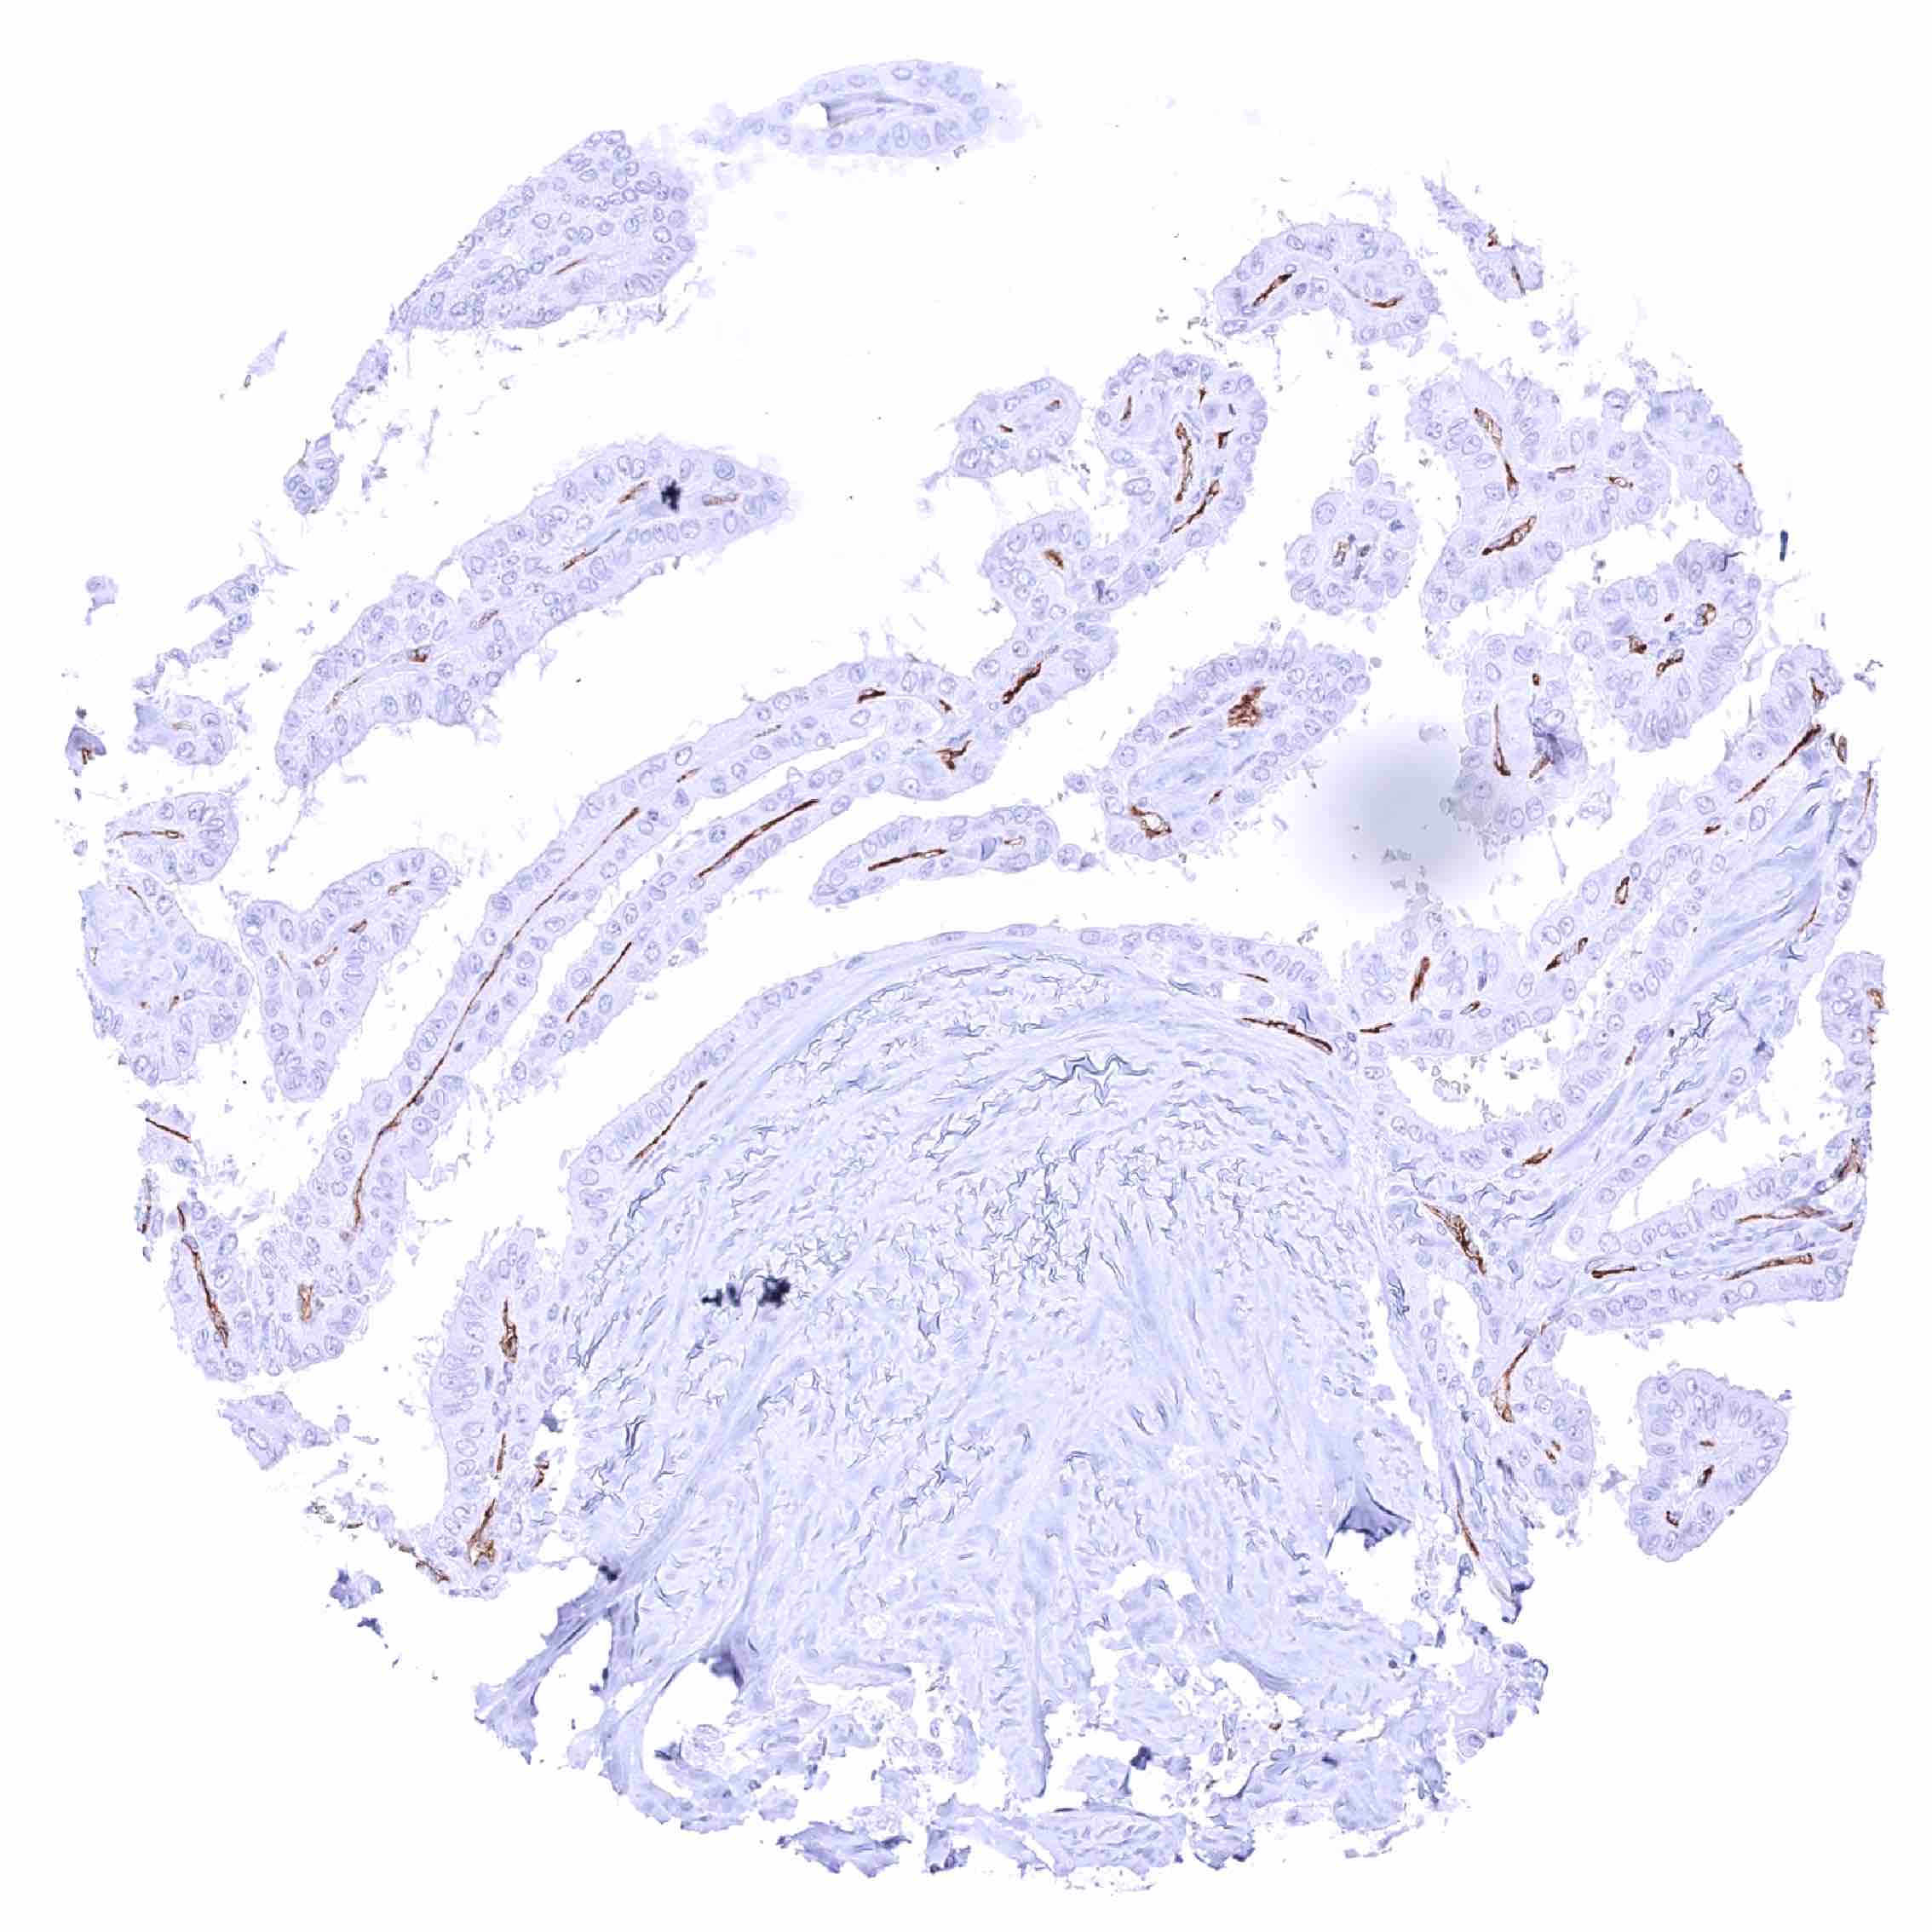

Thyroid – PODXL negative papillary carcinoma. Distinct PODXL positivity of endothelial cells of tumor associated vasculature.